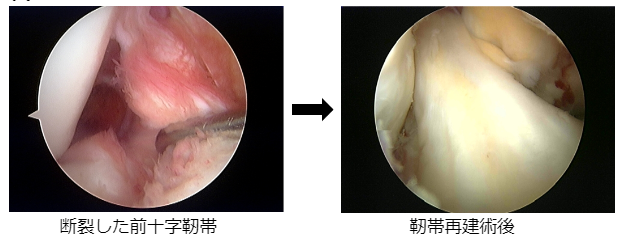

スポーツ外傷による膝前十字靭帯損傷、半月板損傷に対しては全例、関節鏡視下手術を行っています。また離断性骨軟骨炎や反復性膝蓋骨脱臼などの疾患に対しても関節鏡を併用し、低侵襲手術を心掛けております。以前と比べ入院期間も著しく短縮され、前十字靭帯の術後は約2週間で退院が可能です。半月板手術は約1週間で退院が可能となっています。